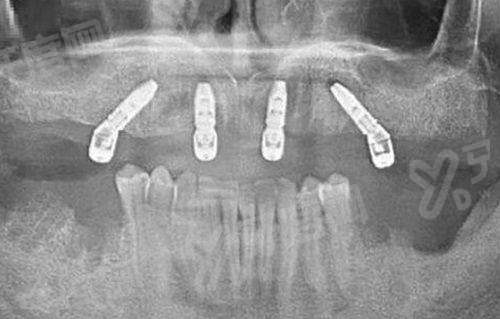

擅长项目:高难度种植牙、全口/半口即刻负重

技术优势:从事口腔临床工作二十余年,精通各种骨量不足条件下的种植方案,手法轻柔,被誉为“种牙快手”,帮助无数缺牙老人重获口福。